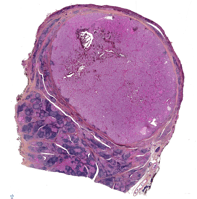

Le cancer de la thyroïde est une pathologie maligne de la thyroïde caractérisée par la prolifération anormale de cellules thyroïdiennes. Il existe différent type de cancer de la thyroïde en fonction du type cellule concerné :

- Cancer papillaire qui représente plus de 80% des cancers de la thyroïde

- Cancer folliculaire

- Cancer médullaire

- Cancer dédifférencié et anaplasique

- Lymphome de la thyroïde

- Un traitement chirurgical (thyroïdectomie totale ou lobectomie thyroïdienne) est réalisé en première intention dans la plupart des cas. Ce geste peut être associé à l’ablation des ganglions lymphatiques qui drainent la thyroïde (curage ganglionnaire).